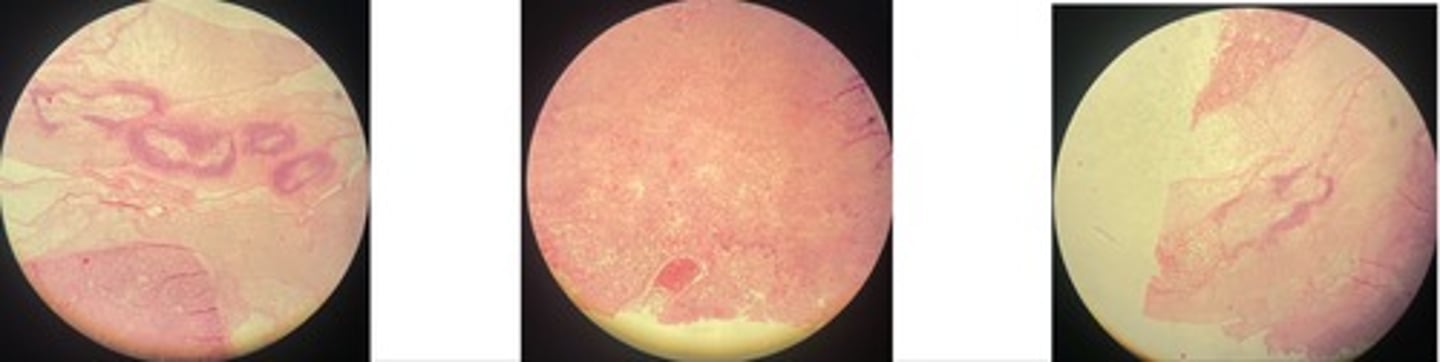

Organisation of fibrin during post-traumatic pericarditis

- heart is covered in fibrin w/ vilious like projections

- young + old granulation tissue

- fat, inflam cells, myocardium

Chronic interstitial pneumonia

- thickened alveolar septa …narrowed lumen

- lymphoid follicles around bvs

- prolif of s.m cells

Parasitic pneumonia

- distended alveoli, bronchi + bronchioles

- degenerated + mononuclear cells

- s.m + epi hyperplasia … thickened alveolar septa

- exudate + emphysema … congestion